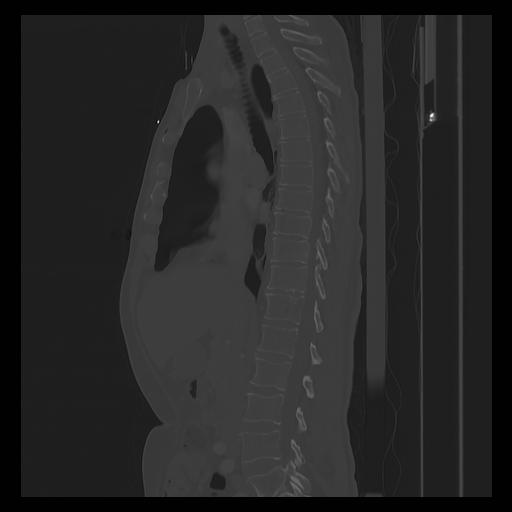

33 PULMON,CE,Sagittal,3.000,PULMON,Sagittal,